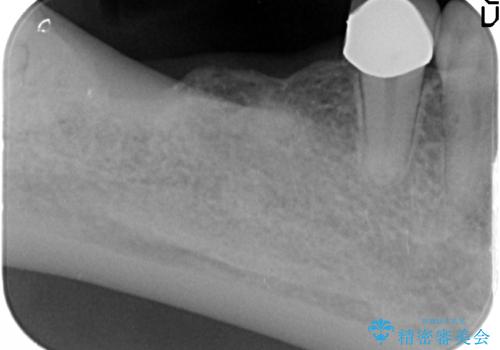

インプラントの埋入には十分な骨量が必要ですが、虫食い状に骨が足りなかった為インプラントの埋入と同時に骨の増成を行いました。

インプラントを埋入する手術と同時に骨の増成を行う場合と、埋入前に骨の造成だけを行う場合があります。